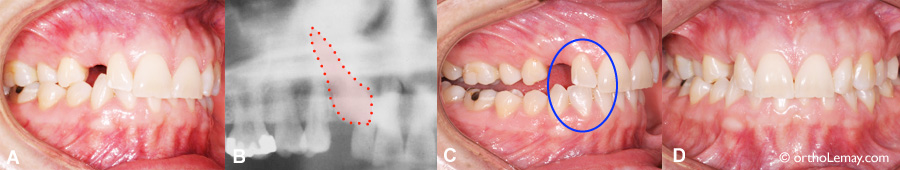

Femme de 26 ans avec une bonne occlusion, sauf pour une canine incluse qui a causé des dommages à l’os et à une dent adjacente. Voir les explications ci-dessous. (Femme – 26 ans)

Cet autre exemple pourrait démontrer ce qui peut arriver au cas précédent s’il était laissé sans supervision pendant plusieurs années.

• (A) Une femme de 26 ans a une condition similaire au cas 1 ci-haut; elle présente une canine supérieure droite complètement formée, mais sévèrement incluse du côté du palais (B-3).

• Cette condition, qui est en progression depuis au moins 15 ans, aurait possiblement pu être évitée avec une supervision adéquate pendant l’éruption des dents (prise de radiographies et extractions sélectives).

• Le fait d’avoir gardé la canine incluse pendant toutes ces années a eu plusieurs conséquences dommageables pour l’environnement de cette dent :

• Avec les années, la canine temporaire est tombée lorsque la canine permanente incluse a progressivement usé sa racine. Il en résulte un espace important et inesthétique où était la canine temporaire (* jaune).

• (B) La canine incluse a résorbé (usé) plus de 40% de la racine de l’incisive permanente latérale supérieure droite. La flèche et la ligne rouges indiquent le bout de la racine usée. La santé et survie de cette incisive latérale sont maintenant incertaines à long terme.

• Un défaut osseux très important (perte d’os visible en foncé sur la radiographie) s’est développé dans la région de la canine droite (* rouge) de sorte qu’une tentative de loger la canine dans l’arcade peut nécessiter une chirurgie pour ajouter de l’os ou être vouée à l’échec.

• En comparaison, la canine gauche est descendue normalement par elle-même (flèche bleue).